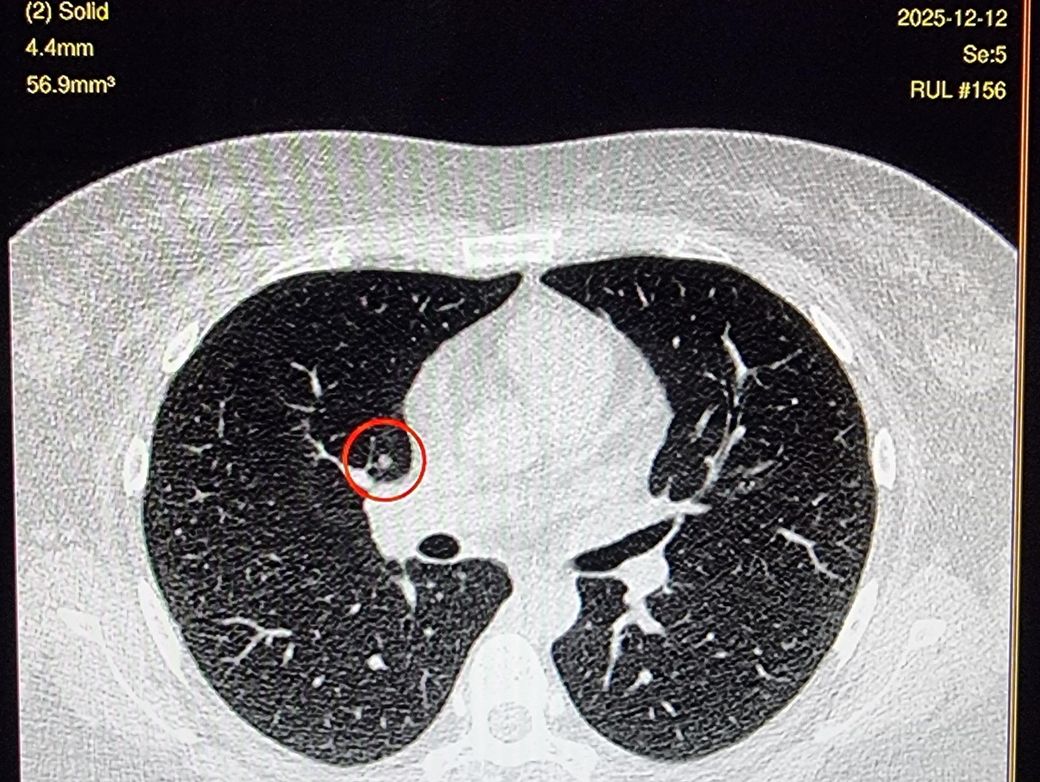

근데 cd를 보니 luCAS-plus란 ai가 찾아낸 오른 쪽 solid 결절 4.4mm가 있더라구요.

(사진이 Ai가 찾아낸거에요)

환자분이 표시를 한 axial image를 보면 결절이 맞는 것처럼 보이기는 합니다. 하지만 이 역시 영상 앞뒤를 모두 확인을 해봐야 합니다. 한 컷의 영상만 가지고는 뭐라 말씀드리기가 어렵습니다.